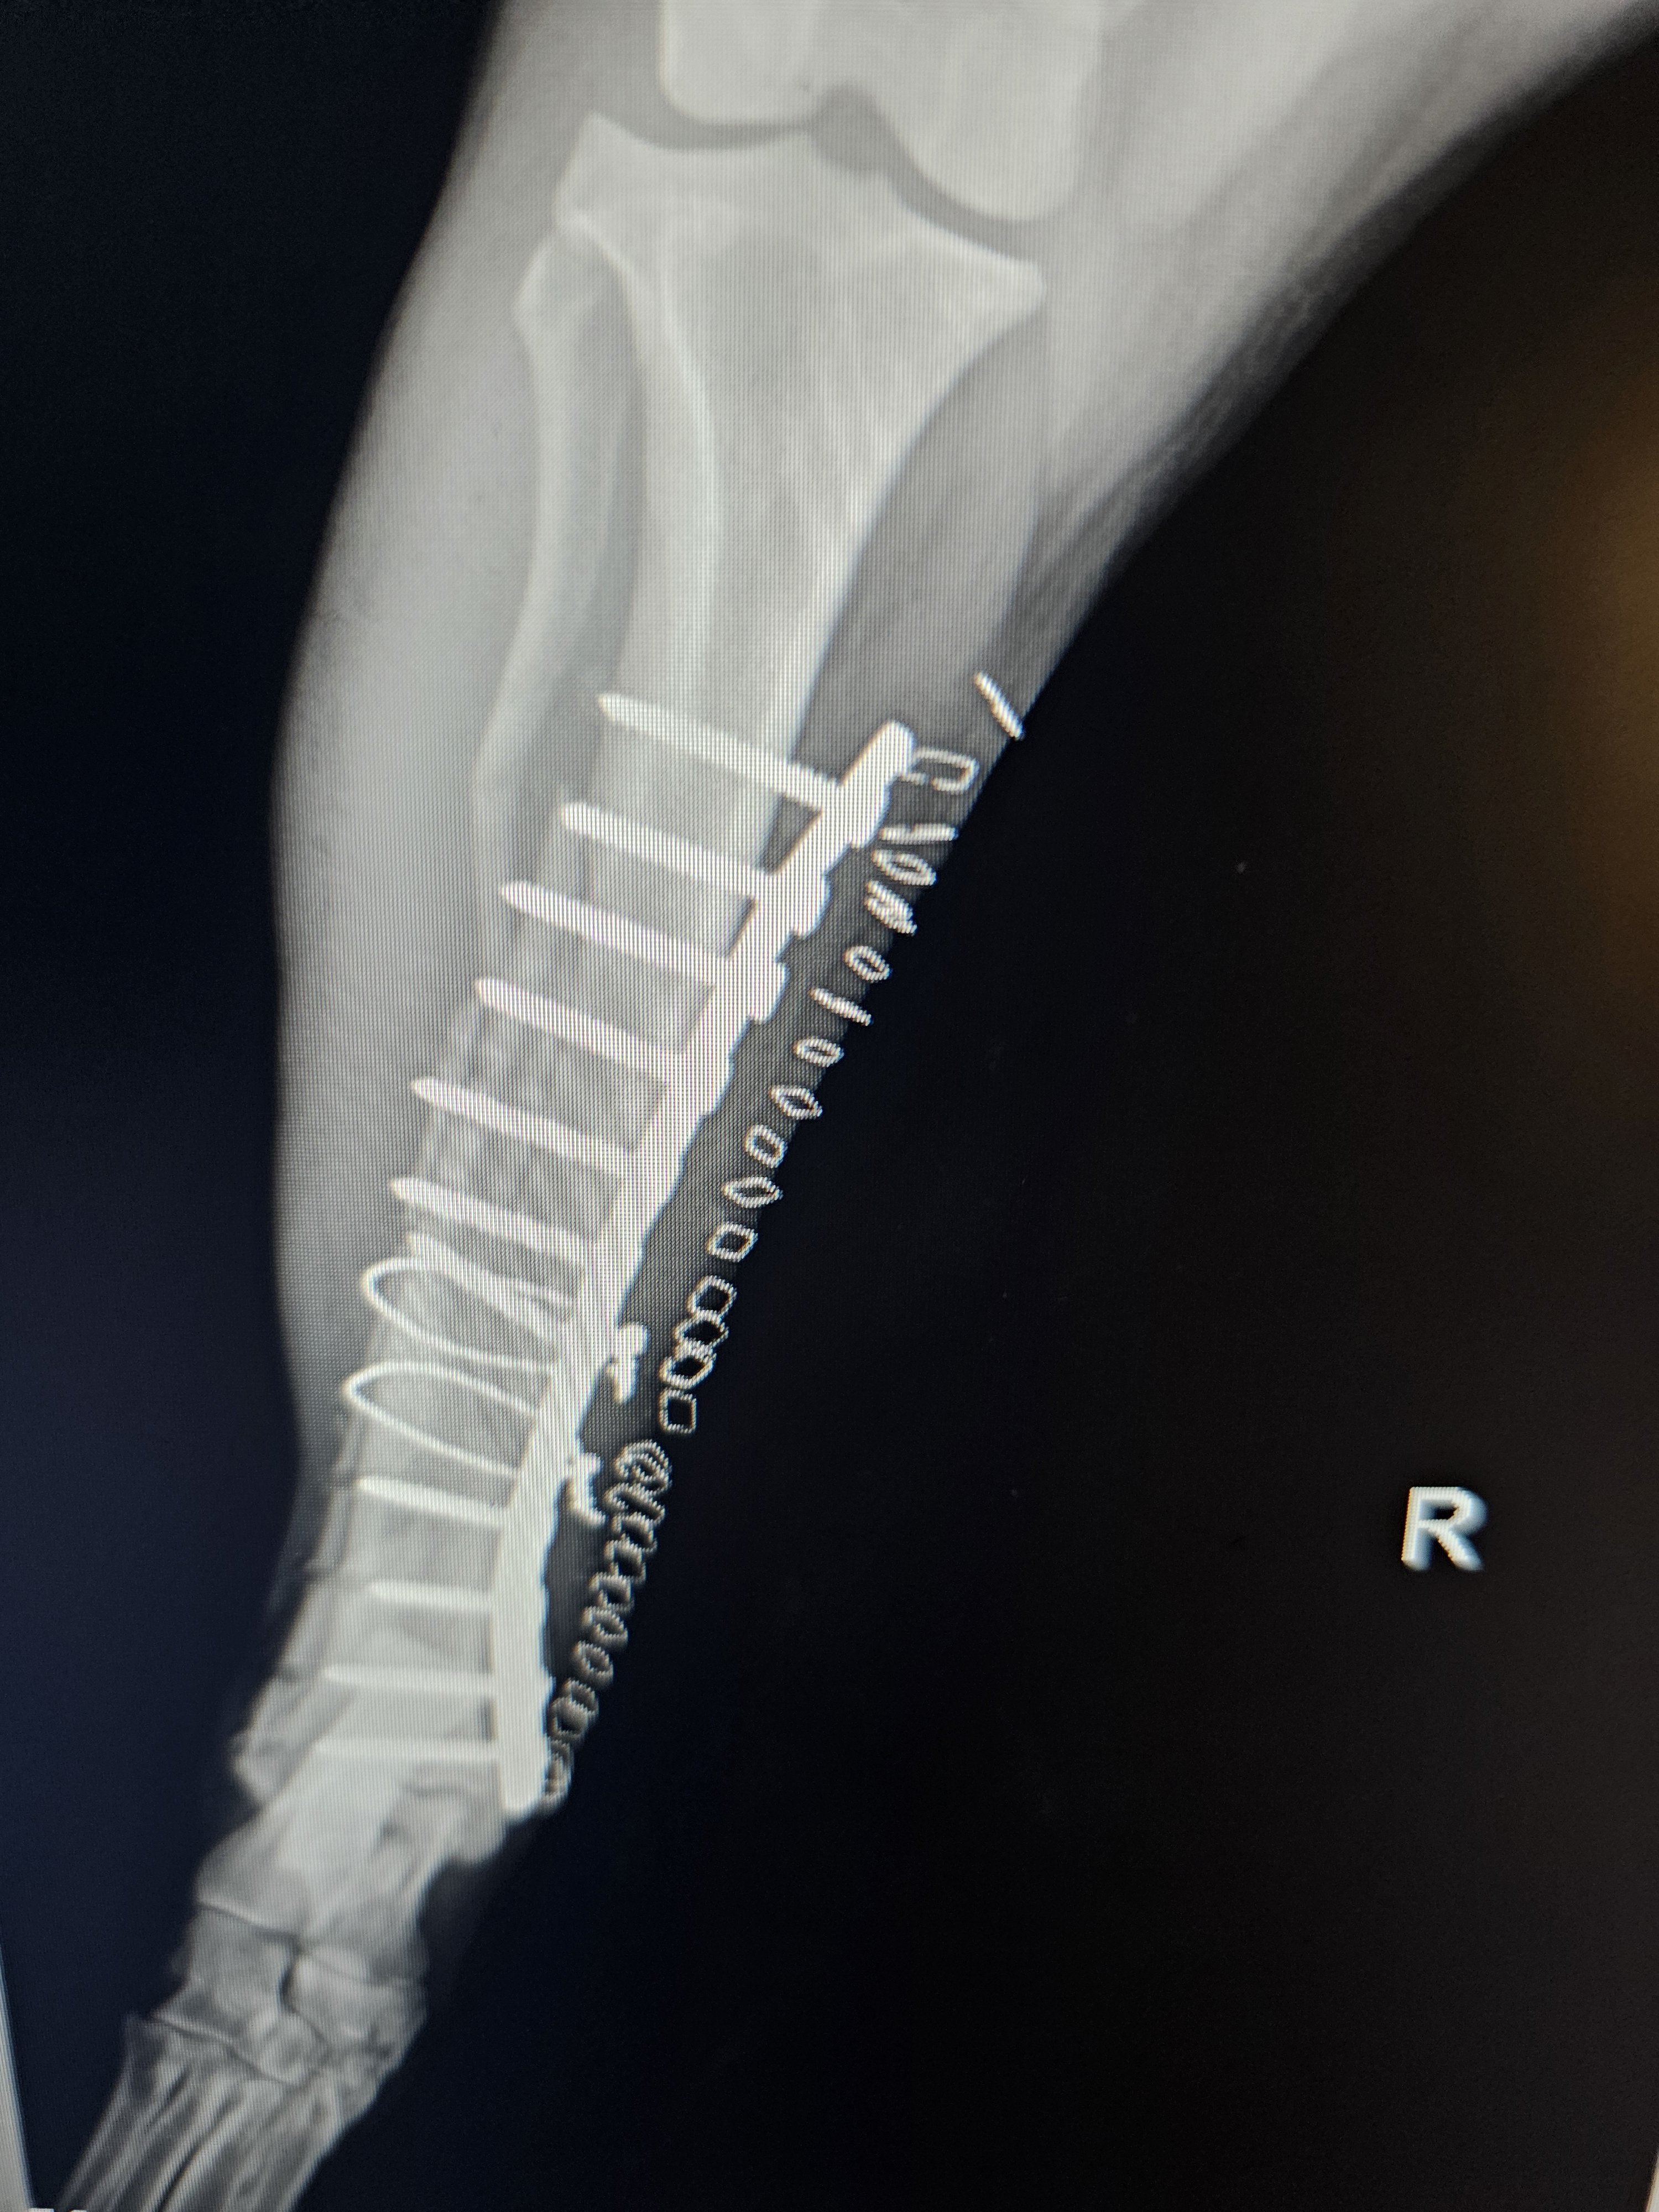

Orthopedic Surgery

Specializing in ACL repairs, knee surgeries, bone plating, and complex orthopedic procedures.

Since graduating from The Ohio State Veterinary School in 1989, Dr. Dan has performed over 1,000 orthopedic procedures — from lizards to llamas. His expertise spans orthopedics, ophthalmology, oncology, and exotic pet care.